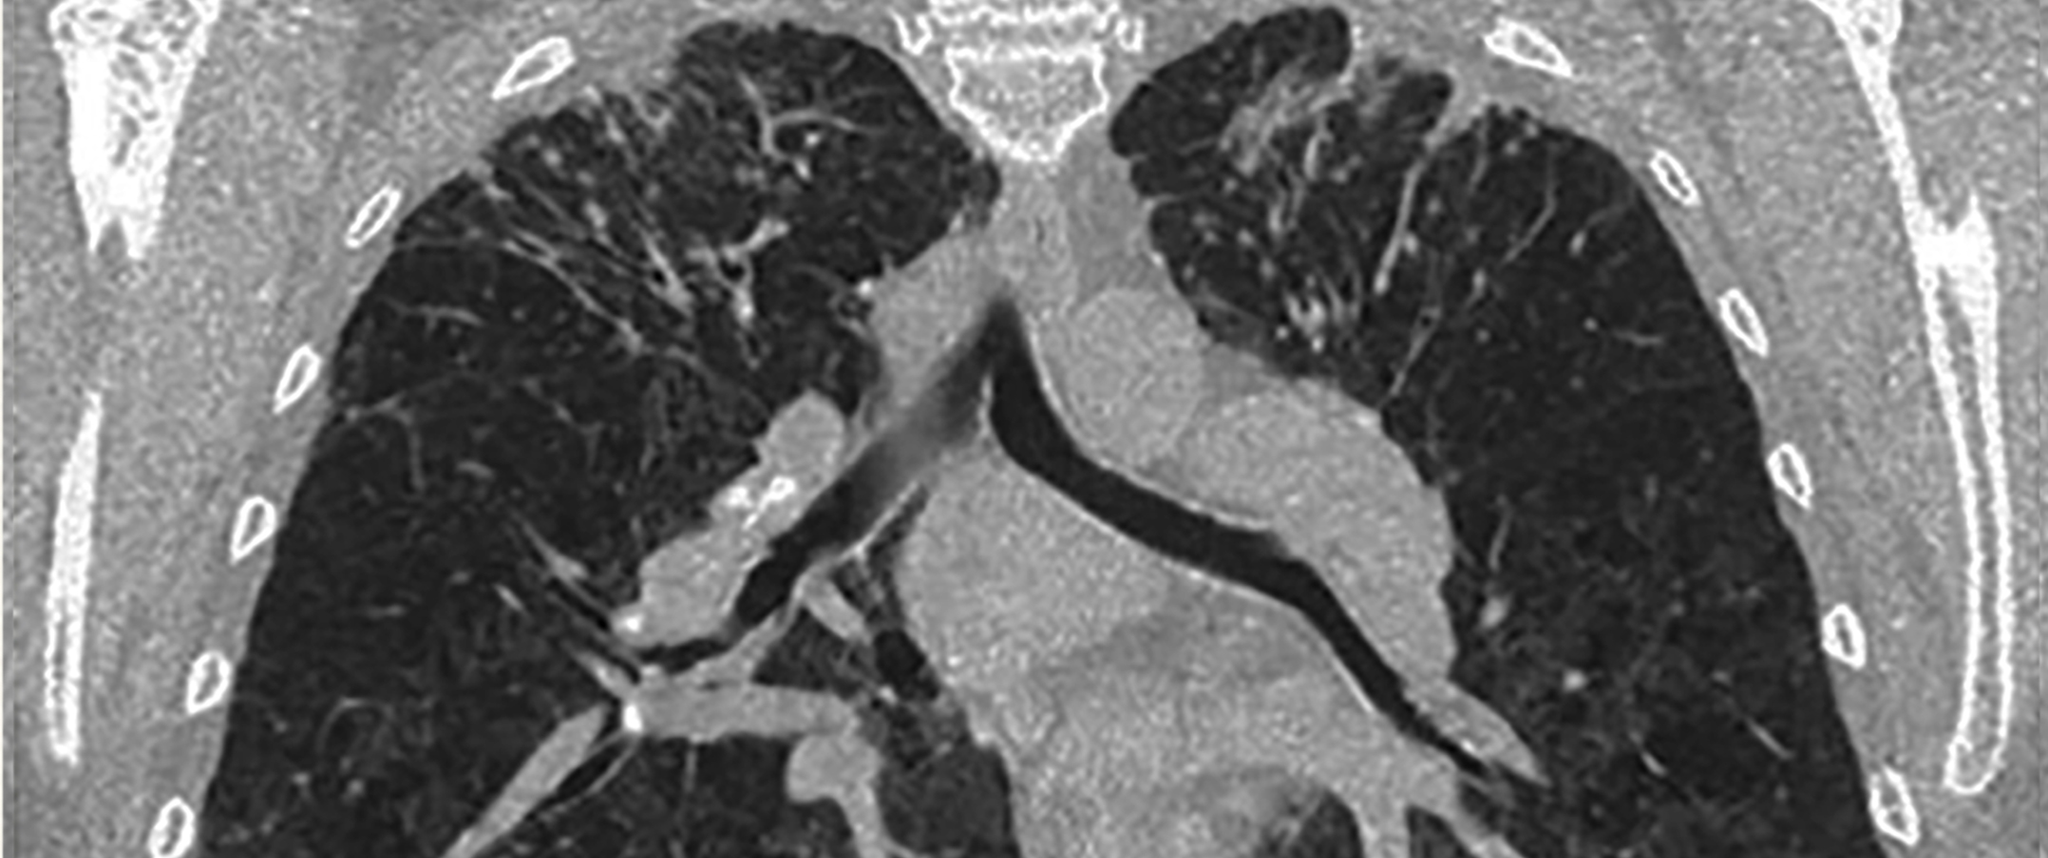

A high-resolution CT lung scan displaying scarring typical of beryllium-induced disease

An X-ray at this time was negative for lesions or opacifications. A high-resolution CT in 2005, however, revealed confluent apical infiltrates in both lungs and evidence of mid-zone granularity. As a result, Mr. W’s pulmonologist diagnosed pulmonary sarcoidosis and referred him to the Harron Lung Center for treatment.